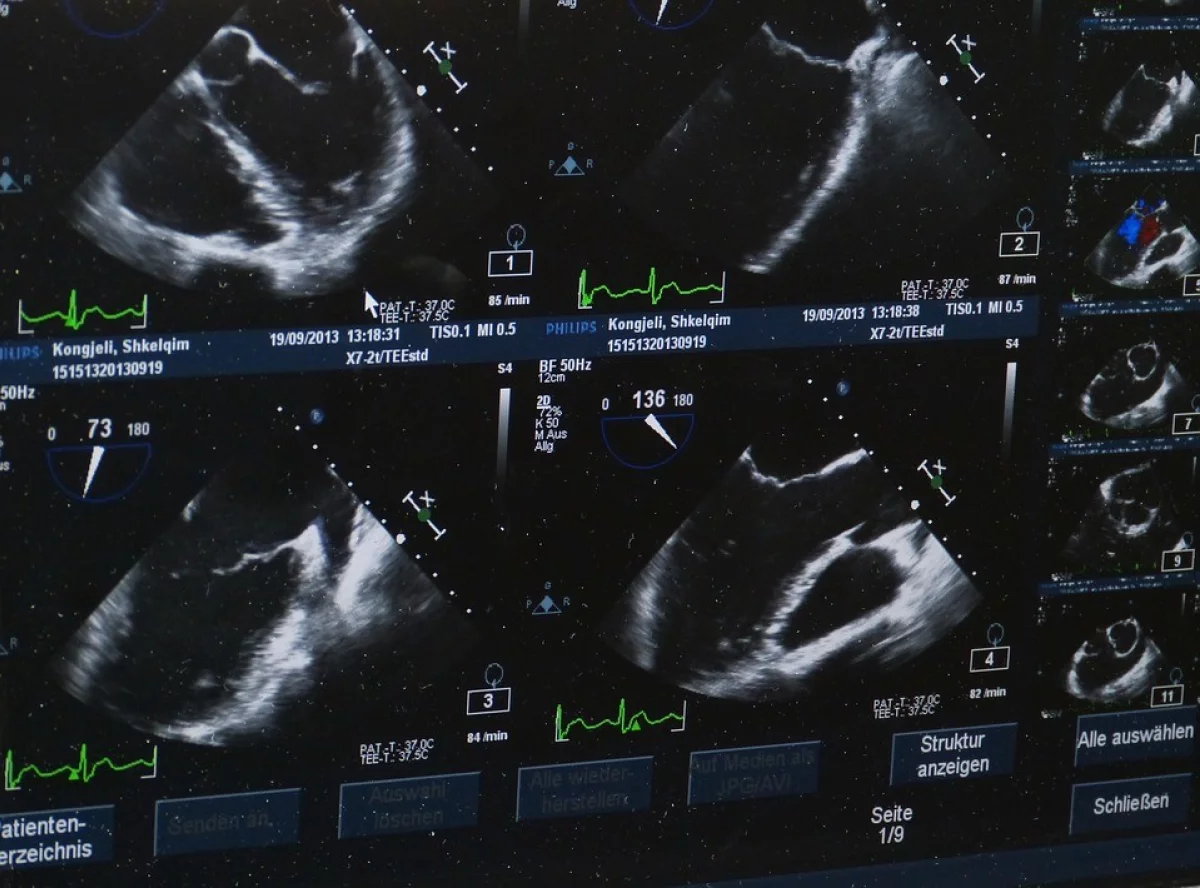

- 30 мая я обратилась в Эс-Класс-Клиник на плановый осмотр после родов, - рассказала Оксана СЕРГЕЕНКОВА. – Были жалобы – слегка болит шов, обильная менструация. После осмотра гинеколога пошла на ультразвуковое исследование (УЗД [ульразвуковая диагностика - прим. ред.]). Врач, показывая на экран, начала рассказывать, как все плохо: детей я больше иметь не смогу, внутри у меня жидкость, гной, а шов настолько воспален, что места живого нет. Да и вообще, воспаление такое жуткое, что если я прямо сейчас не начну лечение, при следующей менструации просто умру. Врач озвучила варианты: лечиться самостоятельно, дома, или же заплатить им 9500 (со скидкой).

- Никакой жидкости. Никакого гноя. Никакого воспаления, - рассказывает она. - А дальше началось самое интересное. Мне было нужно получить на руки свои страшные диагнозы. В итоге выслали. На заключении нет печати врача, а заключение с УЗД - не распечатка с датчика, а бумажка от руки. Да и как они смогли бы дать мне нормальное заключение, если в кабинете УЗД ничего не печатали?